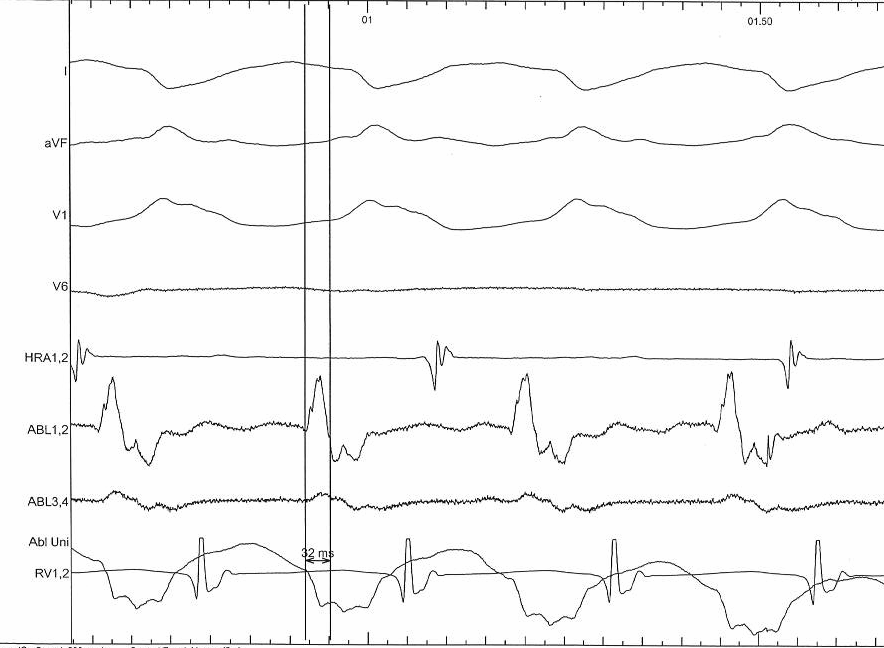

Electrograms - accessory pathway

unipolar_ap.png

Electrograms - VT

unipolar_vt.png